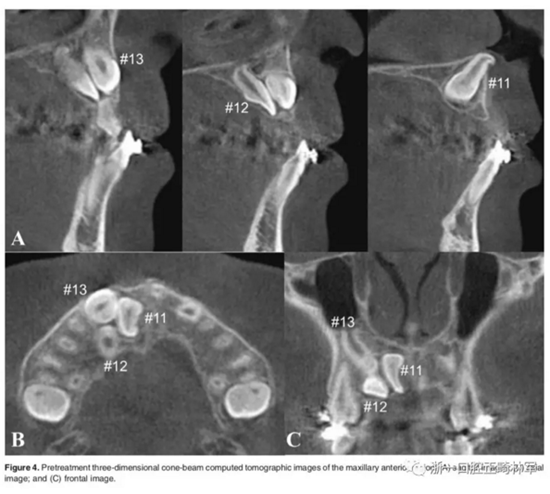

影像檢查:

全景X片及CBCT示:11-13復雜阻生,上頜前牙區(qū)牙槽骨水平不足;11阻生,遠中旋轉(zhuǎn)90°,牙冠朝向腭側,根尖位于鼻底、前鼻棘皮質(zhì)骨內(nèi),牙根形態(tài)彎曲;12、13不完全易位,12位置偏腭側,13位置偏舌側,12的牙根形態(tài)也較彎曲。

影像學:頭顱側位片示:矢狀向和垂直向骨骼發(fā)生變化(ANB角,3°;SN-MP,51°);上頜切牙略前傾(U1-SN,106°),與下頜切牙一致(IMPA,75°);病人的面部輪廓得以保持。全景片示:由于牙齒萌出,上前牙區(qū)垂直向牙槽骨水平增加;雖然前牙牙根較彎曲,但其平行度仍可,且無明顯的牙根吸收。CBCT示:前牙唇側骨質(zhì)連續(xù)性改善,牙根唇側支持組織變好,牙槽骨高度、厚度均有增加,但轉(zhuǎn)矩的改變一定程度上導致了局部應力的增大。

l 三維向分析可保證精確的診斷,恰當?shù)纳锪W,以及軟硬組織的生物學改建。

l 治療前,所需的評估包括:阻生牙埋伏深度,受影響的牙近遠中位置,受影響的牙整體位置,牙根間距,牙根彎曲程度,根吸收、開窗風險,外科牽引手段,牽引機制,以及牙周手術的必要性。